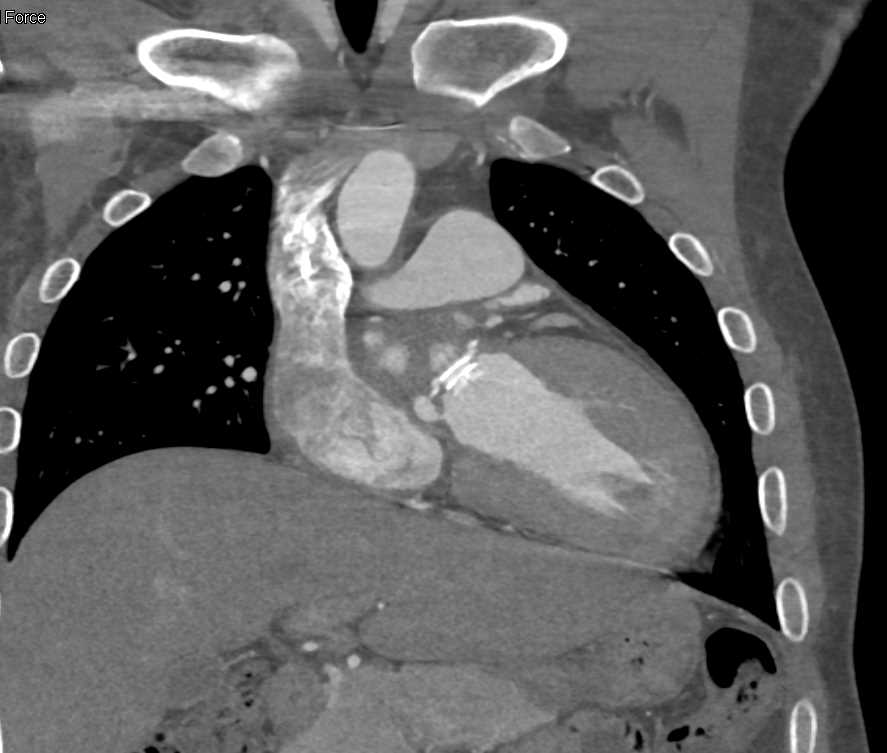

Aortic Valve Repair